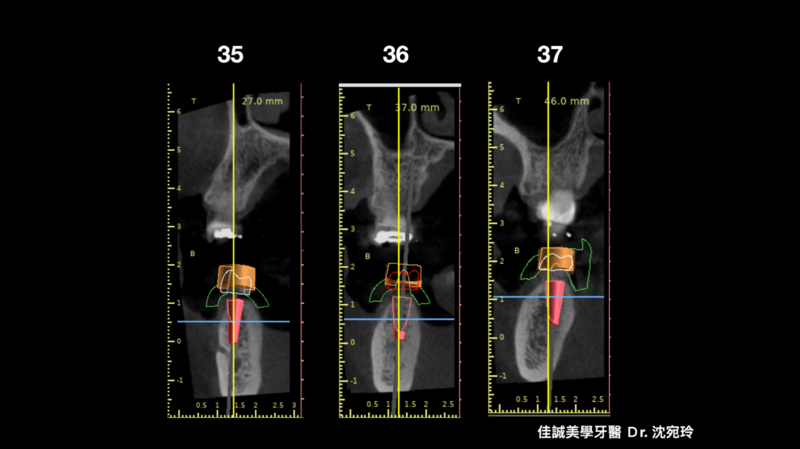

以這個案例,我們量測了牙脊缺牙區的總寬度,再精算植體間距和植體寬度,後牙區小臼齒種植寬度長度4 mm X 11.5mm的植體,大臼齒則置入兩支寬度長度5 mmX11.5mm的植體,而在設計時在軟體內要讓三顆植體盡可能平行,以利將來植牙贋復製作,減少應力集中造成植體周圍炎的可能。我們利用模子的STL檔和斷層掃描的DICOM檔做疊合,在Bluesky軟體內,由醫師自己設計出最佳的植體位置、寬度長度,再請專業的3D列印公司做數位模板輸出。因為在軟體內我們已經看出將來植體的位置和需補骨的量,進而反推切線的位置,最後我們知道角質化上皮終究都需要補一場,於是治療計畫一開始就是先補上角質化上皮,等四個月後軟組織穩定,我們接著利用手術導板植入三個植體,並於當次補入骨粉和再生膜,術後如我們預期,傷口恢復良好。